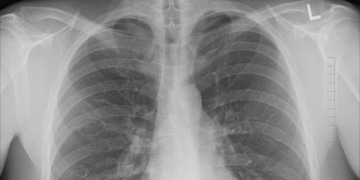

O Instituto Português de Oncologia do Porto (IPO-Porto) vai participar num estudo europeu de medição de resultados e de custos no cancro do pulmão, cujo lançamento decorreu no último dia 18 de junho, em Madrid. Além da instituição, fazem também parte outros hospitais de referência, no trabalho promovido pela International Consortium for Health Outcomes Measurement (ICHOM) e pela All.Can. O IPO-Porto vai implementar o projeto na Clínica do Pulmão durante o ano de 2019.

Os resultados do ensaio de Fase III KEYNOTE-407 demonstram que pembrolizumab, o anti-PD1 da MSD, quando em combinação com quimioterapia, melhora significativamente a sobrevivência global no tratamento de primeira linha do cancro do pulmão de células não-pequenas metastático escamoso (CPCNP). As conclusões foram divulgadas na Reunião Anual 2018 da ASCO, que decorreu em Chicago entre 1 e 5 de junho, pela MSD.

Pembrolizumab, o anti-PD1 da MSD, melhorou significativamente a sobrevivência global (OS) e a sobrevivência livre de progressão (PFS), enquanto tratamento de primeira linha do cancro do pulmão de células não-pequenas escamoso (CPCNP), no ensaio de Fase III KEYNOTE-407. O estudo, realizado pela MSD com base numa análise interina conduzida pelo Comité de Monitorização de Dados, concluiu que pembrolizumab combinado com quimioterapia tem resultados de OS e PFS significativamente mais longos do que a quimioterapia isolada.

A Comissão de Trabalho de Bronquiectasias da Sociedade Portuguesa de Pneumologia (SPP) vai realizar a sua reunião anual já no próximo dia 2 de junho. A imagem no estudo das bronquiectasias e as recomendações europeias para abordagem destas doenças são dois dos temas que vão estar em destaque no encontro.

A Formação Contínua Pós-Graduada – Prática Clínica, sobre o tema “Desafios na Comunidade: Pneumonia Aguda e Tuberculose na Criança” vai realizar-se no próximo dia 22 de junho, na sede da Sociedade Portuguesa de Pediatria (SPP), em Lisboa. O evento resulta de uma iniciativa da Sociedade Portuguesa de Pneumologia Pediátrica (SPPP).

A MSD anunciou recentemente os resultados do KEYNOTE-189, um estudo piloto de Fase III que avalia pembrolizumab, terapia anti-PD-1 da MSD, em combinação com pemetrexed e cisplatina ou carboplatina para o tratamento de primeira linha do cancro do pulmão de células não-pequenas (CPCNP) metastático. Os resultados demonstraram que a combinação de quimioterapia pembrolizumab-pemetrexed-platina melhorou significativamente a sobrevivência global (OS), reduzindo o risco de morte para metade em comparação com a quimioterapia isolada.